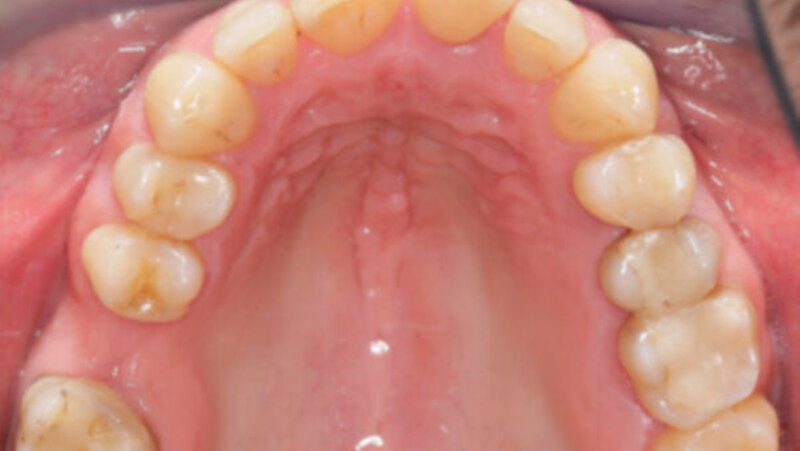

Das Fallbeispiel beschreibt das Vorgehen bei einem 38-jährigen, gesunden Patienten mit einer Einzelzahnlücke in Regio 16 (Abbildung 1). Laut Anamnese lagen keine Kontraindikationen für eine Implantation vor. Es bestand eine suffiziente Mundhygiene. Alle notwendigen Vorbehandlungen waren abgeschlossen. Das Implantat konnte wie geplant inseriert und nach Abschluss einer dreimonatigen Einheilzeit mit einer transokklusal verschraubten monolithischen Keramikkrone aus Lithiumdisilikat versorgt werden. Seit der Implantation im Mai 2019 wurden keine Komplikationen dokumentiert.

Intraorale Ausgangssituation und Wax-up